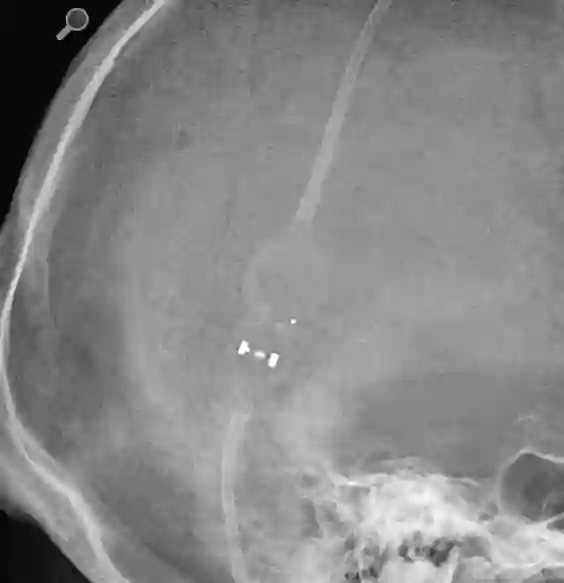

Röntgenaufnahme eines Codman Certas Plus Shuntventil, welches auf Druckstufe 4 eingestellt ist.